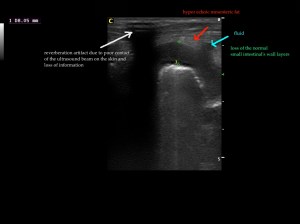

Findings: The ultrasound exam revealed a marked distention of a segment of the small intestine which ended in a narrowed lumen due to a thickened wall. The mesenteric lymph nodes were markendly enlarged and hypoechoic. A fine needle aspirate was performed.

After we decided the path of the needle, the insertion site was prepared with the Hibitane scrub and alcohol. Then we applied some gel on the Linear probe and covered with the elastic glove. Then the syringe was loaded with 5ml of air and attached to the needle. We performed techniques with and without aspiration depending on the blood that sometimes was withdrawn. The diagnosis was Lymphoma.

The GIF shows the frames from the normal small intestinal layering to the thickened abnormal wall in a perpendicular view.